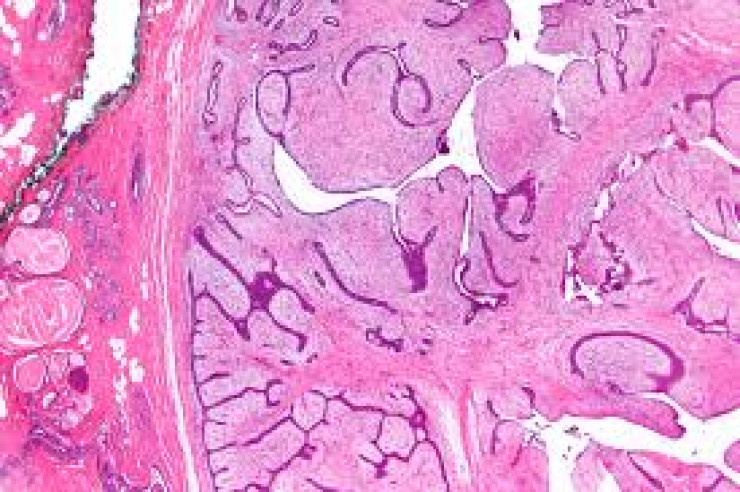

Ο Φυλλοειδης όγκος είναι ένας σπάνιος όγκος που μοιάζει πάρα πολύ με το συνηθισμένο ινοαδένωμα και έχει παρόμοια εικόνα τόσο στην κλινική εξέταση όσο και στον απεικονιστικό έλεγχο.Ούτε η μαστογραφία αλλά ούτε και ο υπέρηχος μαστών δεν μπορεί να ξεχωρίσει αν αυτό που απεικονίζεται είναι ένας φυλλοειδής όγκος ή ένα ινοαδένωμα. Αυτό πού κάνει τον φυλλοειδή όγκο να ξεχωρίζει από το ινοαδένωμα είναι το συνήθως μεγάλο μέγεθος του και η ταχύτητα με την οποία αυξάνεται.

Άρα λοιπόν ο φυλλοειδής όγκος είναι ένας σπάνιος όγκος που προσομοιάζει απεικονιστικά απόλυτα με το ινοαδένωμα και πρέπει να αντιμετωπίζεται άμεσα και ριζικά με σκοπό να μειωθούν οι τοπικές υποτροπές που δεν είναι καθόλου σπάνιες σε αυτούς τους όγκους.